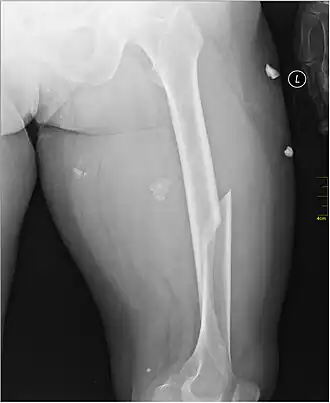

Fractura de fémur

Una fractura de fémur es la rotura del fémur. Puede ser una fractura por fragilidad, debido a una caída o traumatismo menor, en una persona con osteoporosis que debilita sus huesos. La mayoría de las fracturas femorales en personas con un hueso normal son resultado de traumatismos de alta energía, tales como accidentes de tránsito.

Existen muchos subtipos de fracturas de fémur, cada una de las cuales tiene un pronóstico y tratamiento diferentes. Se conocen comúnmente como "fracturas de cadera", aunque en realidad este nombre no es correcto, pues lo más frecuente es que no se afecte la articulación.